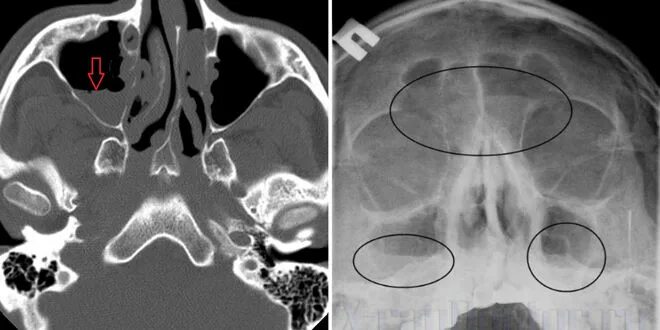

Рентгенография придаточных пазух носа синусит. рентгенография околоносовых пазух гайморит. рентген пазух носа расшифровка гайморит. гайморовы пазухи рентген описание.

Рентген пазух носа гайморит. гайморовая пазуха рентген. фронтит снимок рентген. острый фронтит рентген.

Рентген носовых пазух гайморит. верхнечелюстной синусит рентген. острый фронтит рентген. рентген пазух носа гайморит снимки.

Патология гайморовых пазух кт. гайморит снимок кт гайморовой пазухи. синусит гайморовых пазух на кт.